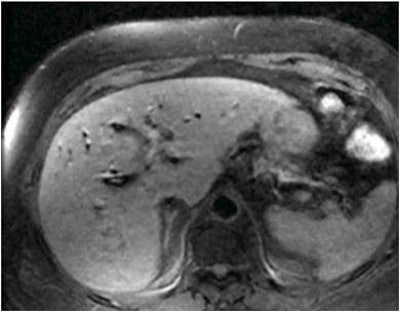

![]() |

| The 3D VIBE MR image (above) shows the difference in data acquired compared to CT with stereotactic body radiation therapy (below). All images courtesy of Dr. John Mikell. |